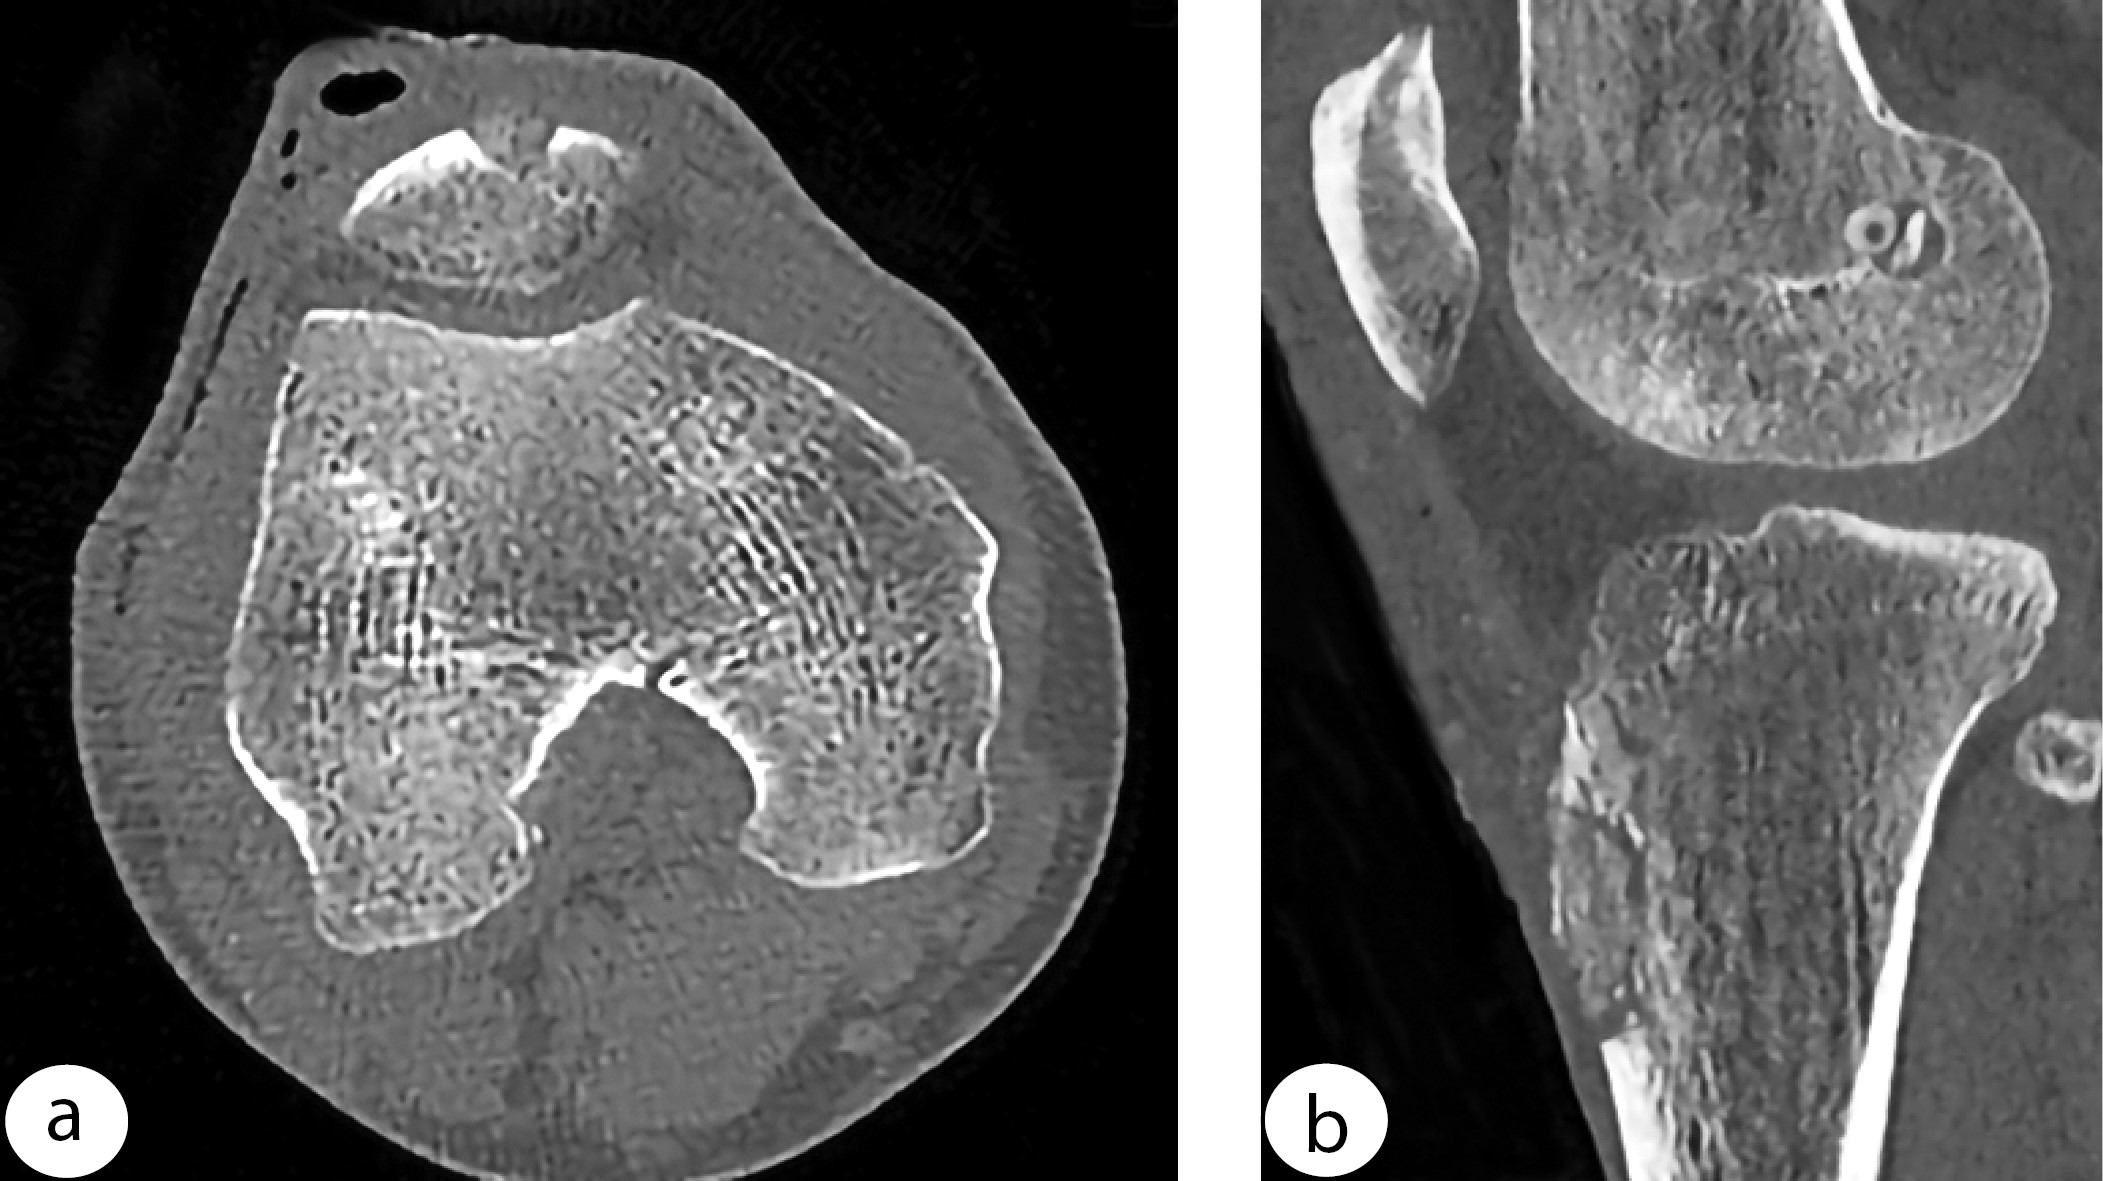

CT evaluation on the day following surgery revealed that bone defects after ligament harvesting were nearly completely filled with cancellous bone, and all graft material was localized within the defect zones (Figure 7). At 6 months, all observations showed that bone grafts had fused with the defect walls and were nearly indistinguishable in density from the surrounding bone, with their surface becoming smoother. No signs of heterotopic ossification were observed (Figure 8).

Figure 7. CT scans showing filled bone defects of the patella (a) and tibial tuberosity (b) on the first postoperative day

Figure 8. Three-dimensional CT reconstruction of the knee joint showing cancellous bone-filled donor defects of the patella and tibial tuberosity 6 months after surgery